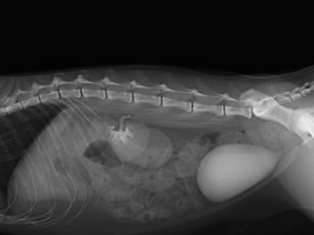

人工尿管(SUBシステム2.0)を設置

尿管結石を取り除き人工尿管(SUBシステム2.0)を設置しました。

水腎症は改善しました。

結石も取り除きの痛みからも解放されて元気に退院してくれました。

新しいSUBシステム2.0を設置

漏れている左尿管を修復しSUBシステム2.0を左右の腎臓に装着しました。

SUBシステムを設置しました。